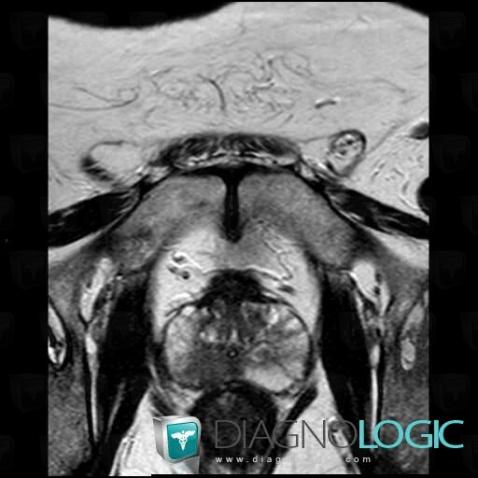

Prostate cancer, Prostate, MRI

Here is the specific information in the key image above:

- Diagnosis Prostate cancer, Location(s) Prostate, with gamuts